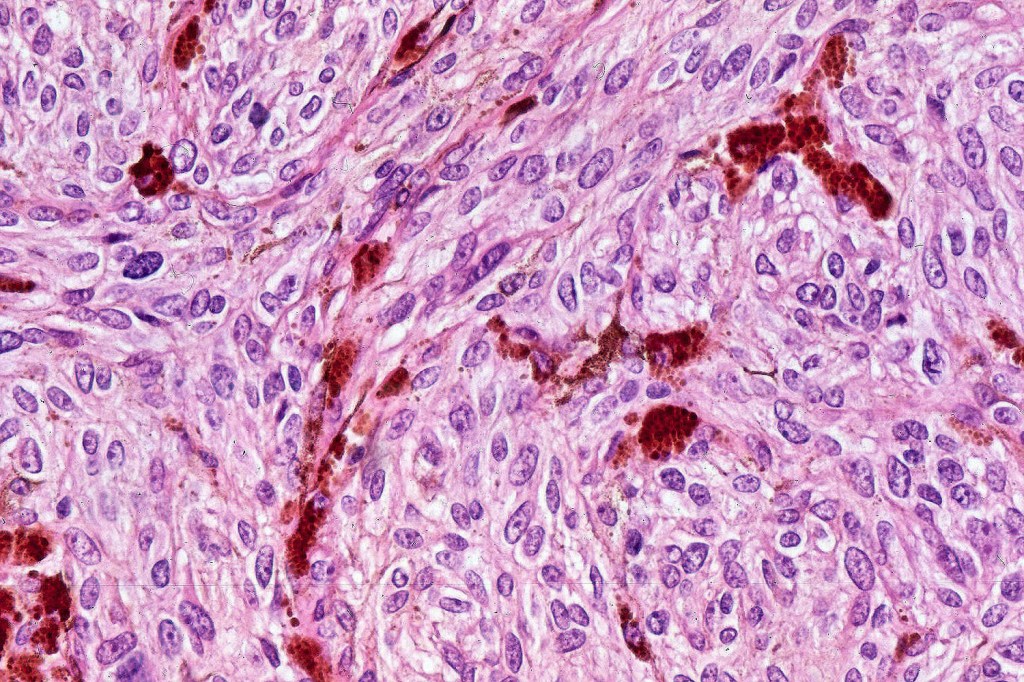

•Admixture of spindle cells, pigmented bipolar or dendritic cells & melanophages

•Cytoplasm is pale and nuclei are small with inconspicuous nucleoli

•An alveolar pattern is characteristic particularly with clear cell nodules

•Mitoses are typically very sparse or absent

•Multinucleate giant cells sometimes present